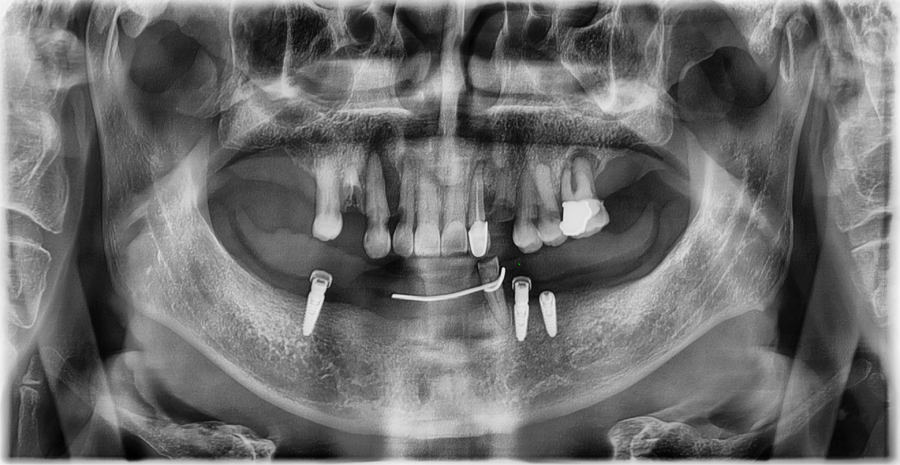

Detailed diagnosis

At our Jamsil dental clinic, Seoul OB Dental Hospital,

even senior patients are carefully assessed for their current dental condition

through a 3D scanner, intraoral endoscopy, and bite examination.

The examination showed that

enough tooth structure remained in the front teeth,

so veneers could be done without excessive reduction,

and the gum condition was also stable.

The bite was also well aligned without any major issues,

so this was a case in which improving only the color and shape of the existing prosthetics

could restore a more natural and balanced front tooth line.